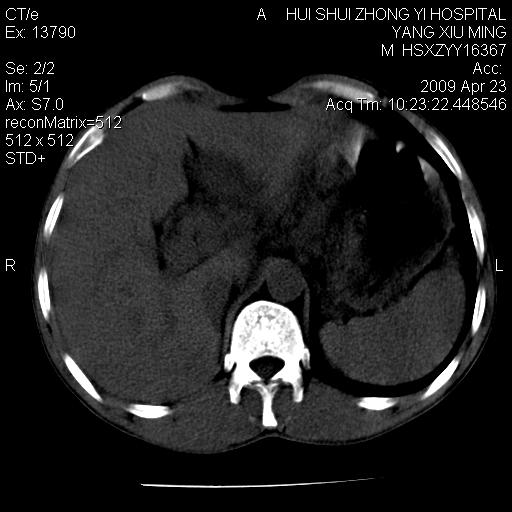

上腹部疼痛一月,呕吐10天,发现左侧颈部包快10天 胸部cr片未见明显异常。

腹膜后淋巴结增大,转移、淋巴瘤?胰腺增大,胰腺炎?占位?颈部考虑增大淋巴结。建议腹部增强扫描。

黑!广泛淋巴结肿大不符合胰腺癌转移。胰腺周围淋巴结肿大致使胰腺看起来大。考虑淋巴瘤可能大。